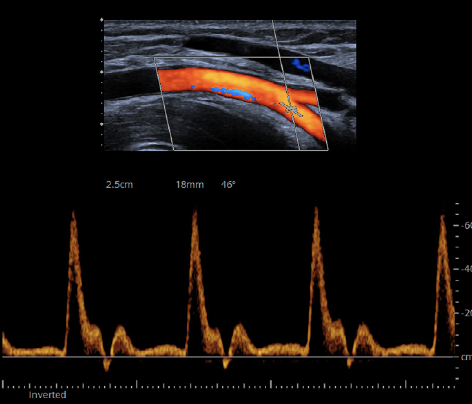

07. ​Digital Ultrasound

Harnessing next-generation BioAcoustic technology, the Sequoia system penetrates deeper with exceptional sensitivity—revealing subtle variations in tissue elasticity, vascular flow, and organ density. Its precision in liver, cardiac, and breast elastography allows Digital Intelligence to detect early micro-imbalances invisible to the human eye.

AI-Driven Cardiac Ultrasound built for cardiovascular excellence integrates more than 5,600 AI-powered measurements informed by nearly two billion cardiac images. Real-time HeartAI mapping provides fully automated view recognition and quantification, reducing human error and standardizing insight across users and systems.